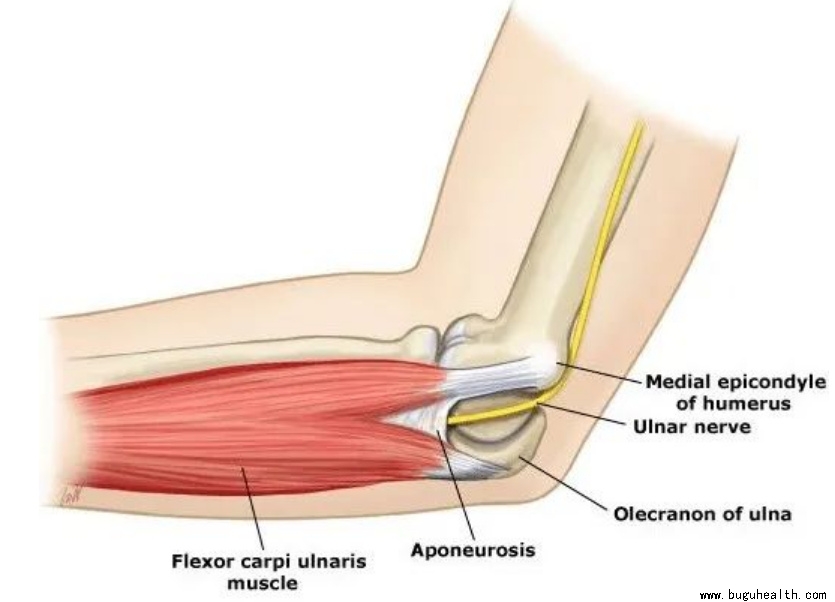

2. 尺骨鹰嘴骨折

属于肘部的骨折!尺骨鹰嘴骨折即是胳膊肘后方凸起处的骨折!症状表现为肘关节局部肿胀、剧烈疼痛,有时断端可触及骨折缝隙,伴随患肢活动障碍。

未移位或可复位则采取保守治疗:若骨折未发生移位,或移位经手法复位可以恢复解剖结构或者功能复位,则可以采取保守治疗;

何时可以进行康复训练?

保守治疗:若患者骨折程度较轻,关节结构较为稳定,4周左右骨折部位会形成骨痂,关节功能得到一定程度的恢复,可以开始进行康复训练。

术后:6周后可以做康复训练。通常两周后可以轻度活动,早期活动度逐步增加,以不疼痛或轻微疼痛为宜。